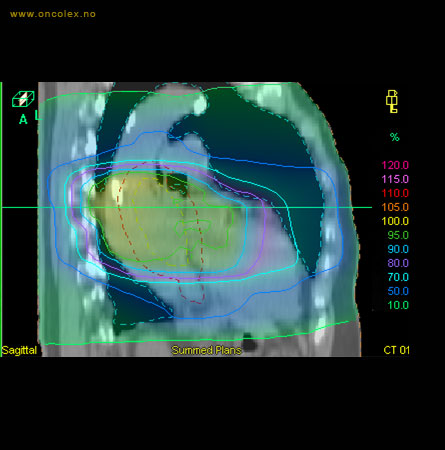

Skisse over hvordan strålefeltet planlegges:

Illustrasjon for målvolum

• GTV (Gross Tumor Volume): Identifisert tumor.

• CTV (Clinical Target Volume) GTV + omkringliggende vev hvor det kan væremikroskopisk spredning.

• ITV (Internal Target Volume): CTV + en indre margin som tar hensyn tilindre bevegelser og endringer av CTV.

• PTV (Planning Target Volume): Innstillingsmargin som inneholder ITV og samtidig tar hensyn til antatte pasientbevegelser, samt variasjoner i pasientopplegging og feltinnstillinger.

• Feltgrense. Tegnes som oftest på kroppen.

ICRU (International Commission on Radiation Units and Measurements)